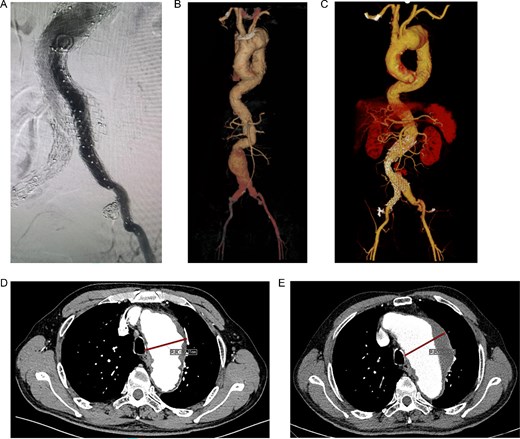

The patient underwent F/B TEVAR on August 17, 2022. Physician-modified stent-graft (PMSG) were deployed in all three branches of the arch. Aortic stent graft from Captivia, Medtronic, USA were utilized; Branch stent graft included iliac artery stent graft and coated stent graft, from Medtronic, BD, etc. Following stent graft placement, angiography revealed unobstructed flow in the three branches of the superior arch, and the arterial aneurysm disappeared completely (see Fig. 2). Due to the twisted aorta, the length of the aortic stent graft delivery system was insufficient, leading to the use of a common iliac artery-artificial vessel approach. The procedure was complicated by anastomosis rupture and massive hemorrhage, requiring a 1000 ml blood transfusion. Post-surgery, the patient was admitted to the intensive care unit and developed a high fever, significant hemoglobin drop, and unstable circulation. An urgent computed tomography revealed a retroperitoneal hematoma, which was removed on August 19, 2022. Intraoperative exploration uncovered a large number of blood clots, totaling ⁓1000 ml, with no obvious bleeding points found. The patient developed bacteremia, pulmonary infection, septic shock, acute kidney injury (KDIGO3 stage), and fungal infection. After long-term supportive treatment, the patient was transferred to a general ward on October 10, 2022, and discharged on October 28, 2022.